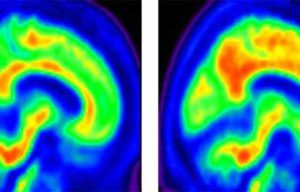

Segundo o estudo, a Aβ pode se aglomerar formando grandes emaranhados de “placas” nas membranas celulares dos neurônios, o que atrapalha na transmissão dos sinais nervosos e pode desencadear a perda de memória, uma das principais características da doença. Essa ligação já havia sido detectada em estudos anteriores, mas não comprovada, devido às limitações tecnológicas.

Conduzida por pesquisadores da Scripps Research, na Flórida, EUA, a pesquisa só se tornou possível por utilizar técnicas de microscopia muito avançadas, com alta resolução de imagens, para poder enxergar as células cerebrais de camundongos e como elas atuavam na produção da beta-amiloide.